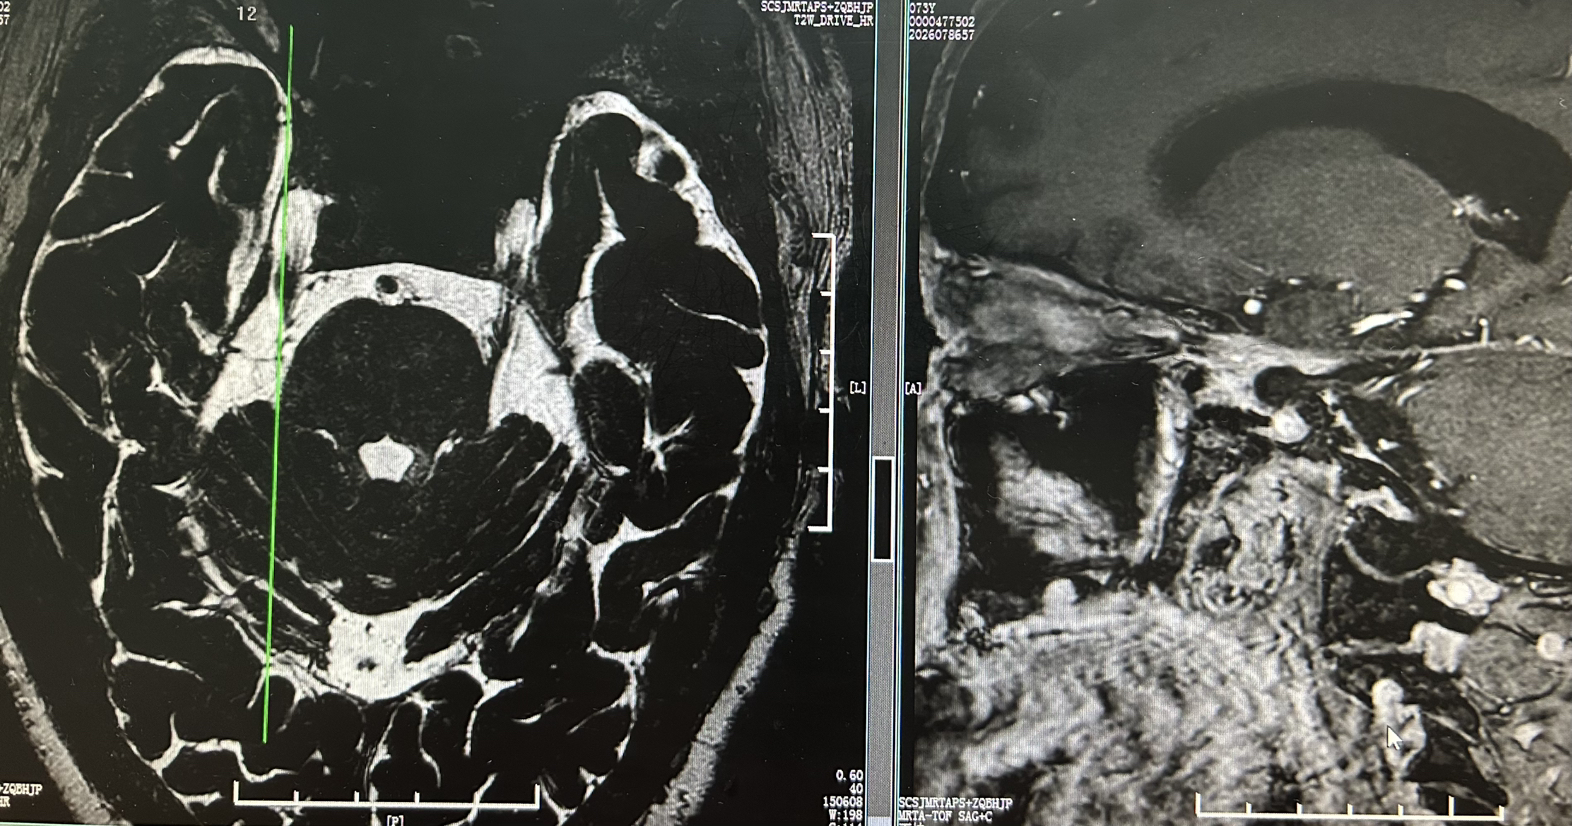

病例“朝花夕拾”潍人医脑肿瘤之经典病例篇——神经内镜下扩大经蝶入路切除实性颅咽管瘤1例

脑肿瘤-颅咽管瘤潍坊市人民医院神经外五科(神经肿瘤病区) 昨天09:49 1081阅读 0评论 8点赞